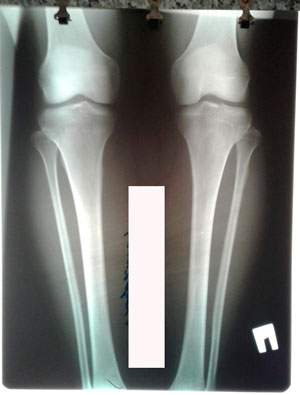

Исходник - 37 лет.

Дата операции - 04.08.2020

Дата снятия аппаратов - 04.12.2020